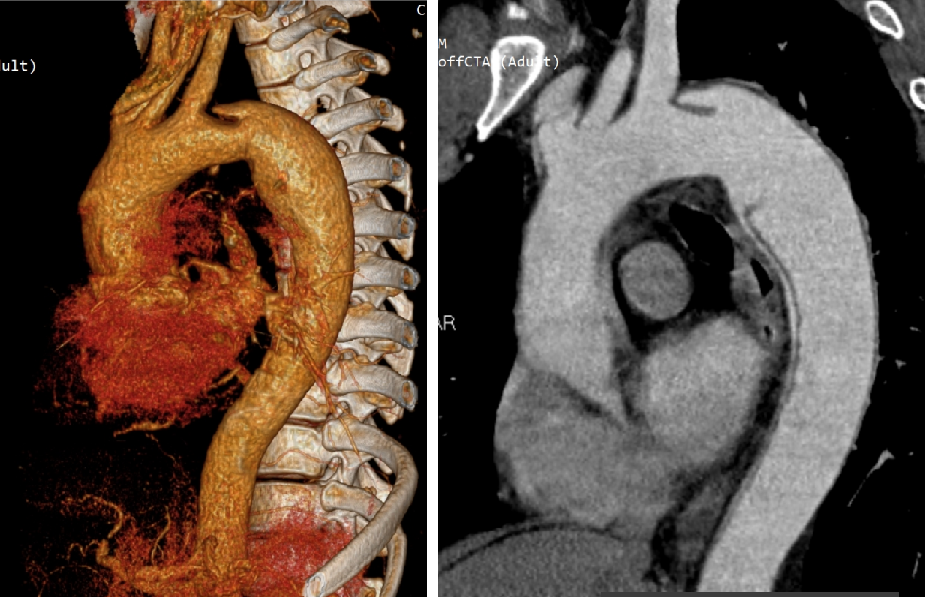

28岁男性,急性复杂型B型AD,急诊TEVAR治疗

48岁男性,胸腹痛20小时,右下肢一过性麻木,TEVAR治疗